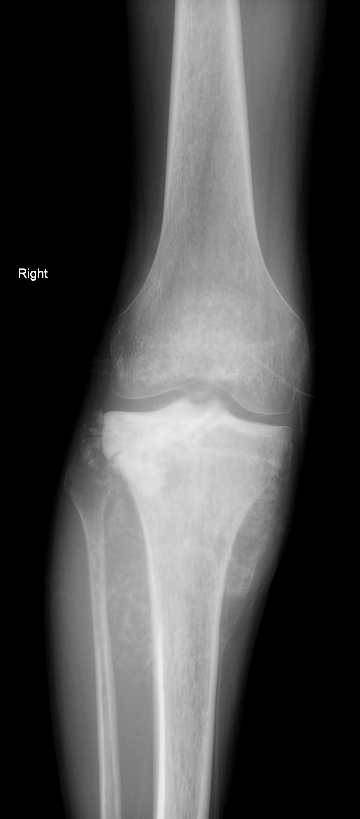

Auch wenn sich Osteosarkom und Ewing-Sarkom bildgebend nicht sicher voneinander unterscheiden lassen, zeigen beide Entitäten charakteristische Häufungen bestimmter morphologischer Merkmale. Auf den beiden vorliegenden Röntgenaufnahmen sehen Sie jeweils eine Knochenläsion – einmal der Tibia und einmal der Fibula. Welche Läsion ist eher einem Osteosarkom, welche eher einem Ewing-Sarkom zuzuordnen, und welche radiologischen Merkmale stützen diese Einschätzung?